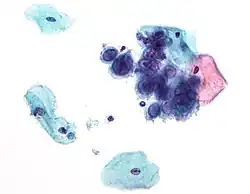

Micrograph of a normal pap smear -

Micrograph of a Pap test showing a low-grade intraepithelial lesion (LSIL) and benign endocervical mucosa. Pap stain. -